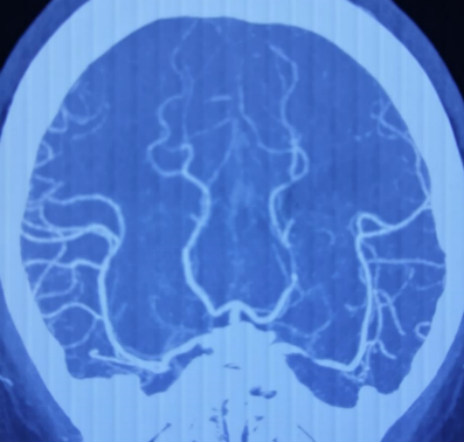

CTA示左侧大脑中动脉主干重度狭窄 2019.6天坛医院

CTP:MTT,TTP延长

术后4个月复查,CTA示支架近端可疑再狭窄 (2020.09,天坛医院)

术后9个月再次复查CTA示左侧大脑中动脉支架内重度狭窄 (2021.02.18天坛医院)